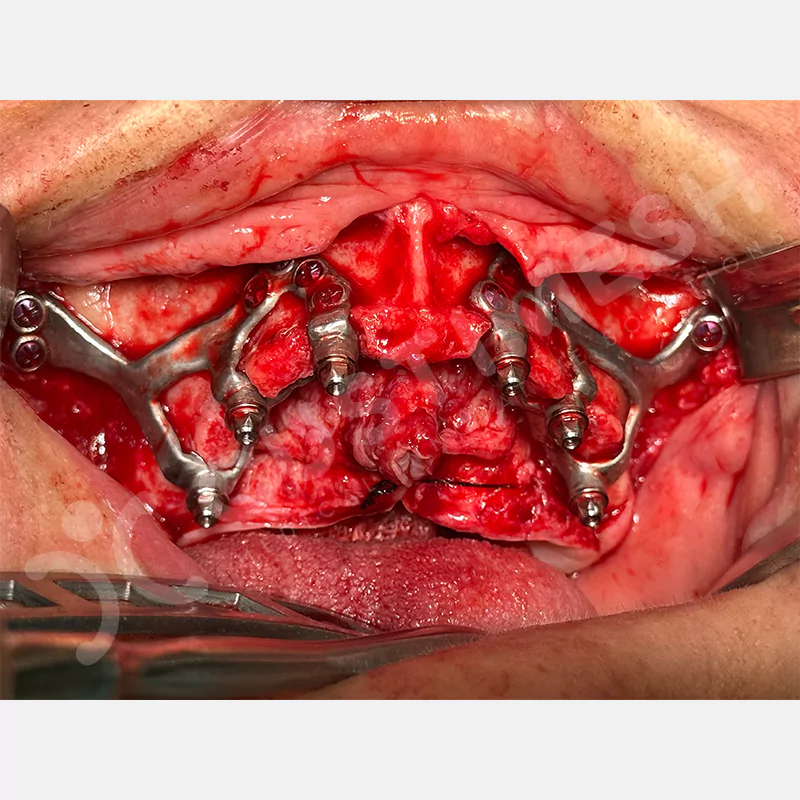

Modern diş hekimliğinde, çene gelişimini tamamlamamış veya ciddi kemik kaybı yaşayan hastalar için kişiye özel titanyum implantlar ile çözüm bulunmaktadır. CAD/CAM teknolojisi ve lazer sinterleme yöntemiyle üretilen bu implantlar, hastanın bireysel anatomik yapısına tam uyum sağlayarak geleneksel implantların uygulanamadığı vakalarda mükemmel bir alternatif oluşturmaktadır. Özellikle ileri derecede kemik kaybı olan hastalar için geliştirilen subperiosteal implantlar, periostun altına yerleştirilerek minimal invaziv bir yaklaşım sunarken, bilgisayarlı tomografi verileri ve sonlu eleman analizleriyle optimize edilmiş tasarımları sayesinde hem estetik hem de fonksiyonel sonuçlar garanti etmektedir. Bu yenilikçi teknoloji, tek seansta implant ve protez uygulamasına imkan vererek hastaların aynı gün doğal gülüşlerine kavuşmalarını sağlarken, kemik greftleme gibi ek işlem ihtiyacını ortadan kaldırarak cerrahi süreci büyük ölçüde kolaylaştırmaktadır. Kişiye özel tasarımı ve üstün biyouyumluluğu sayesinde, daha önce tedavisi mümkün görülmeyen kompleks vakalarda bile başarılı sonuçlar sunan bu implantlar, modern diş hekimliğinde yeni bir çağ açarak hastaların yaşam kalitesini artırmayı hedeflemektedir.

VAKA 1

VAKA 2

VAKA 3

VAKA 4